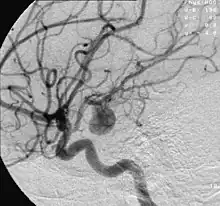

Circle of Willis Arteries beneath brain | |